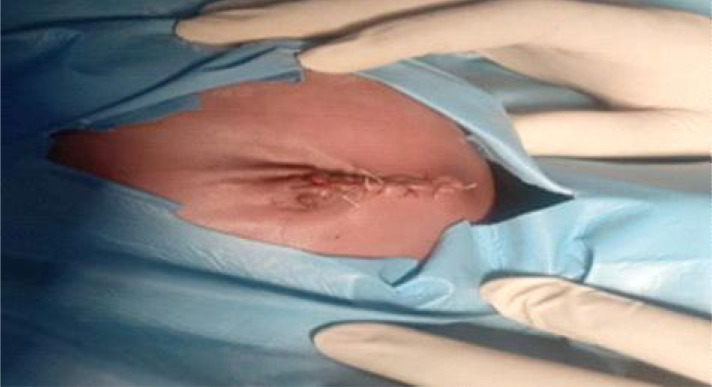

Case presentation: He is a 4-day old male with obstructed CHUC. He had an oedematous umbilical stump, with circumferential normal abdominal wall skin folds in the form of a collar wrapping round the proximal aspect of the protrusion. The umbilical defect measured about 4 cm in diameter. Subsequently, surgical reduction and repair of defect was done, with resolution of symptoms.